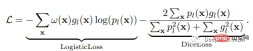

损失函数

神经网络的训练需要一个损失函数来计算模型误差。训练的目标是最小化预测输出和目标输出之间的损失。我们的模型使用Dice Loss 和Weighted Logistic Loss的联合损失函数进行优化,其中权重补偿数据中的高类不平衡,并鼓励正确分割解剖边界。